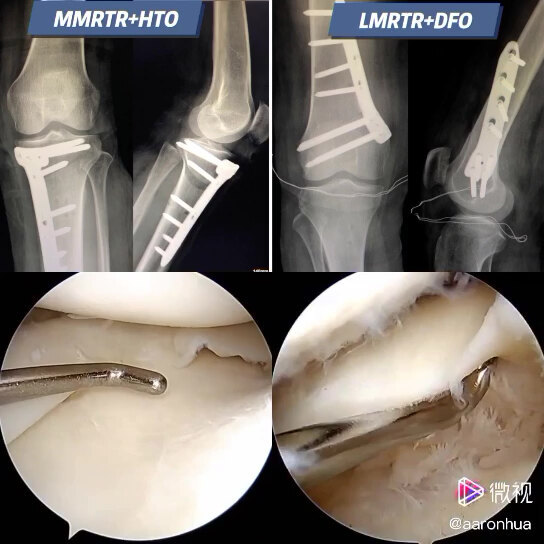

- 患者:男 30岁 双膝疼痛1年,加重3月 最后交流时间 10.18双膝疼痛1年,加重3月 1年前因打羽毛球后出现双膝疼痛,断断续续,状态好时走路基本无... 了解目前膝盖病情严重程度,提供后续治疗建议及重点注意事项总交流次数13已给处置建议